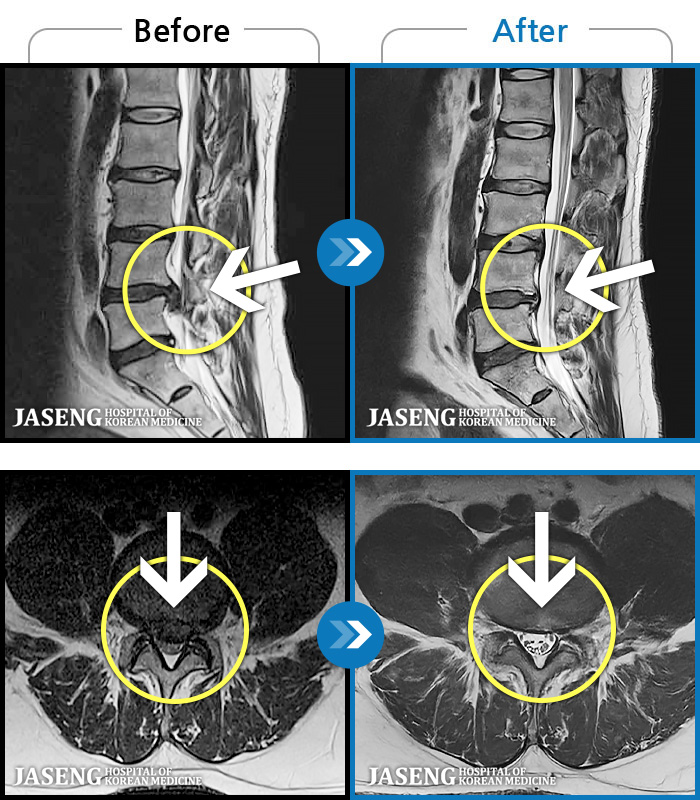

ȯںп Ǹ ǿ ԿǾ, ο ġ ۿ Ƿ ġḦ Ͻñ ٶϴ.